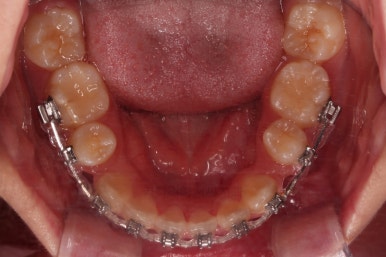

초진 시, 입 안의 모습입니다.

치아가 많이 삐뚤어요.

공간이 부족해서 앞니가 앞으로 많이 뻐드러졌고, 삐뚤한 양상 때문에 덧니가 되었네요.

어금니 맞물림도 좋지 못한 앵글씨 2급 부정교합 상태였어요.